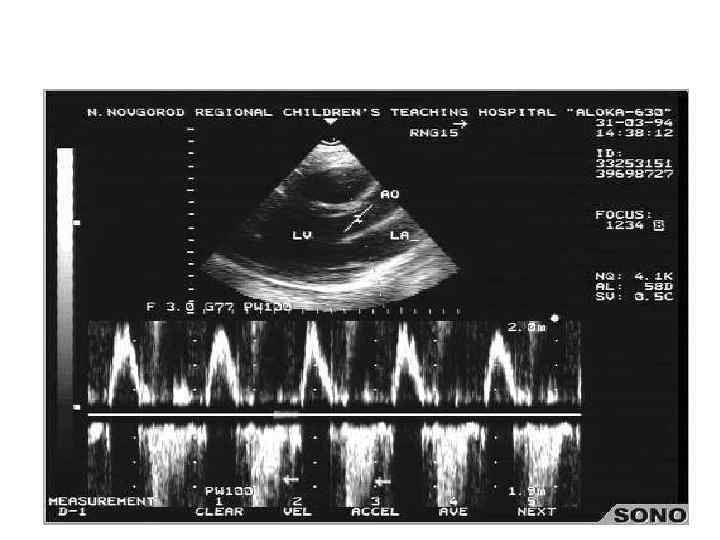

Критерии диагностики инфекционного эндокардита • Для установления диагноза при невыявленном возбудителе используют диагностические критерии. Большие критерии: • 1) положительные результаты посева на гемокультуру из 2 и более раздельных культур крови, не связанные с определенным видом возбудителя; • 2) эхокардиографические признаки инфекционного эндокардита: вегетации на клапанах сердца или подклапанных структурах, . Малые критерии: • 1) предшествующее поражение клапанов или внутривенное введение наркотиков; • 2) температура выше 38°С; • 3) сосудистые симптомы: артериальные эмболии, инфаркты легких, микотические аневризмы, внутричерепные кровоизлияния, симптом Лукина; • 4) иммунологические проявления: гломерулонефрит, узелки Ослера, пятна Рота, ; • 5) спленомегалия; • 6) анемия: снижение уровня гемоглобина крови ниже 120 г/л

Критерии диагностики инфекционного эндокардита Определенный (доказанный инфекционный эндокардит) • Большие клинические критерии: • 1) + гемокультура из 2 раздельных культур крови типичных возбудителей ИЭ в пробах, полученных с интервалом 12 ч, или во всех 3 (а также в большинстве из 4 и более) посевах крови, осуществленных с интервалом более 1 ч; • 2) эхокардиографические признаки инфекционного эндокардита: вегетации на клапанах сердца или подклапанных структурах,

Малые клинические критерии: • • • 1) предшествующее поражение клапанов или внутривенное введение наркотиков; 2) температура выше 38°С; 3) сосудистые симптомы: артериальные эмболии, инфаркты легких, микотические аневризмы, интракраниальные кровоизлияния, симптом Лукина; 4) иммунологические проявления: гломерулонефрит, узелки Ослера, пятна Рота, ревматоидный фактор; 5) положительная гемокультура, не соответствующая требованиям больших критериев; 6) эхокардиографические признаки, не соответствующие большим критериям. • инфекционный эндокардит считается доказанным, если у больного одновременно имеются 2 больших критерия, 1 большой и 3 малых или 5 малых критериев.

Вегетации на створках митрального клапана

Вегетации на створках аортальных полулуний